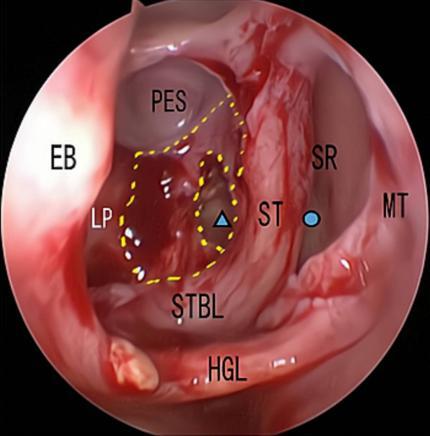

摘要:目的 探究经中鼻甲基板入路的手术技巧及临床效果,旨在系统评估一种兼具良好手术视野和微创性的蝶窦开放径路。方法 回顾性分析2019年9月-2023年9月该院收治的35例孤立性蝶窦病变或单侧蝶窦伴毗邻筛窦受累患者的临床资料,均经中鼻甲基板入路的“四步”程序化操作开放蝶窦。观察手术相关情况和并发症发生情况;采用视觉模拟评分法(VAS)评分,评估头痛和流涕等症状改善情况;采用改良隆德-肯尼迪(MLK)评分,评价术腔恢复状况。结果 所有患者术中保留钩突、中鼻甲和筛泡,26例(74.3%)保留上鼻甲;所有患者均达到临床治愈标准,表现为:术腔引流通畅,黏膜完全上皮化,以及蝶窦开口维持良好开放状态。术后病理显示:蝶窦霉菌病19例(54.3%),蝶窦息肉7例(20.0%),蝶窦黏膜慢性炎症9例(25.7%)。所有患者均未发生严重并发症,仅1例(2.9%)于术后12 d出现中鼻甲创面渗血,经电凝止血后治愈。头痛VAS评分由术前的(4.71±1.66)分,降至术后的(0.83±0.39)分,手术前后比较,差异有统计学意义(t = 13.71,P < 0.01);流涕VAS评分由术前的4.00(0.00,6.00)分,降至术后的0.00(0.00,1.00)分,手术前后比较,差异有统计学意义(Z = -4.47,P < 0.01);手术前后嗅觉减退VAS评分比较,差异无统计学意义(P > 0.05)。MLK评分由术前的4.50(2.00,4.00)分降至1.00(0.00,1.00)分,手术前后比较,差异有统计学意义(Z = -5.20,P < 0.01)。结论 经中鼻甲基板入路蝶窦开放术,严格遵循鼻窦解剖层次,在最大限度地保留鼻腔生理结构的前提下,可获得理想的术野暴露。该术式对于局限于蝶窦及后组筛窦的病变,具有确切的临床疗效。值得应用于临床。